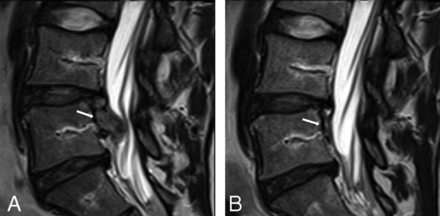

Images of disc herniation from 1 participant with LBP showing evidence of definite change.